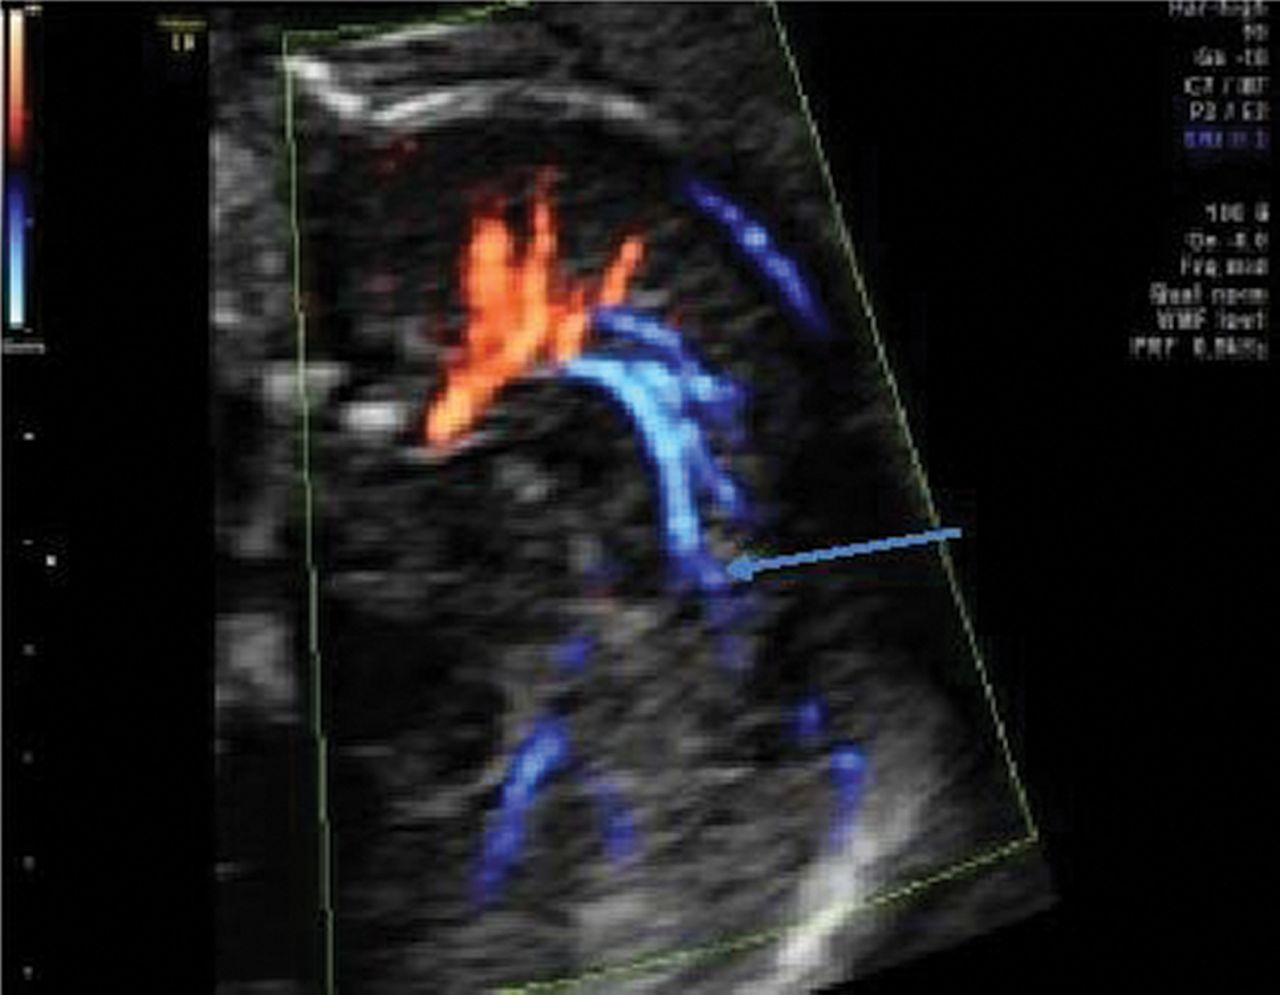

The precuneal artery (arrow) can be observed from 16 weeks onward, and this artery was visible in midtrimester in 80% of our fetuses.

Indirect appreciation of the developing CC will be seen by demonstration of the pericallosal artery and its branches. Recently, color Doppler mapping documented the modified arterial vascular supply with loss of the semicircular loop in CC agenesis (Fig 12).25 In a partial agenesis of the CC, the paracentral artery follows the anterior part of the CC but loses its normal course when the CC vanishes. At this level, the artery moves in an upward and posteriorly oblique direction (Fig 13).19,20 The corpus callosum formation is associated with a medial and upward rotation of the cingulate gyrus, with consequent formation of the cingulate sulcus. In cases of an absent CC, the cingulate gyri do not rotate and are small due to hypoplasia. In cases of partial agenesis, we expect therefore a shorter length of the pericallosal artery as well as a different branching pattern and course. Knowledge of the development and variations in the different branches may enhance the diagnosis of partial agenesis of the corpus callosum.